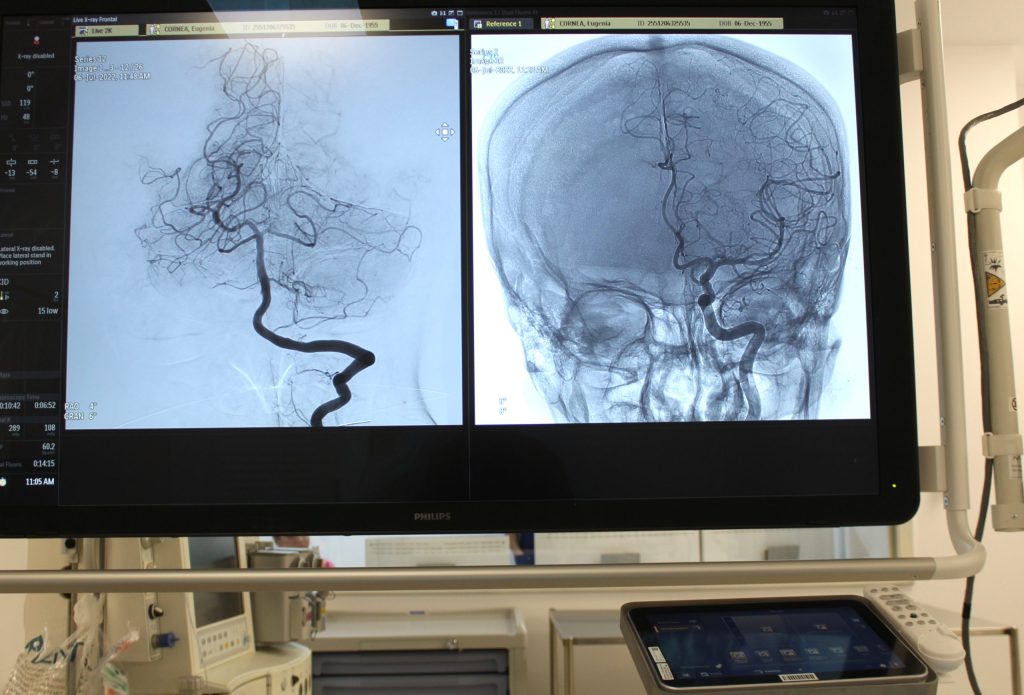

În acest context, a fost lansată în SEAP o licitație publică pentru achiziția celui de-al doilea angiograf, cu o valoare estimată de 9,09 milioane lei. Termenul limită pentru depunerea ofertelor este 3 martie 2026. Primul angiograf biplan a fost achiziționat în 2022 și permite intervenții endovasculare moderne, precum extragerea cheagurilor sau montarea de stenturi.